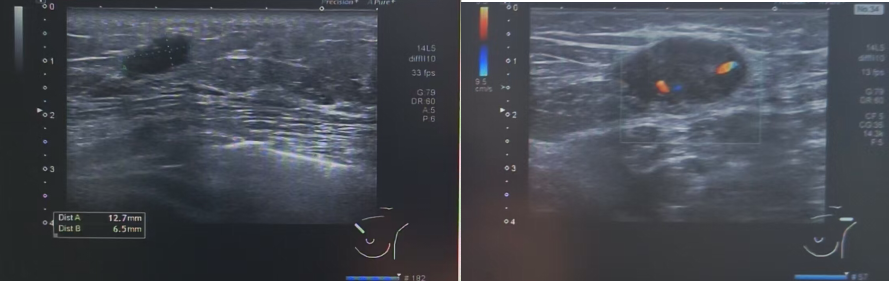

乳腺彩超(2024年05月24日 我院):

图 乳腺彩超(2024年05月24日 我院)

(左):左侧腋窝淋巴结3.93*2.40cm;(右):右侧腋窝淋巴结2.44*0.99cm

1、右侧胸壁可及低回声结节,大小约2.04*0.46cm,边界欠清,形态不规则。

2、胸骨偏右侧皮下脂肪层可及多发低回声结节,较大者约0.91*0.42cm,中间高回声,外周低回声,边界欠清,形态不规则,未见明显明显异常血流信号。

3、左乳11点距乳头2.0cm可及低回声结节,大小约1.75*0.99cm,形态规则,边界清,周边可及高回声声晕,血流信号较丰富。

4、双侧腋窝处可及多发低回声结节,右侧较大者约2.44*0.99cm,左侧较大者3.93*2.40cm,边界欠清,形态不规则。